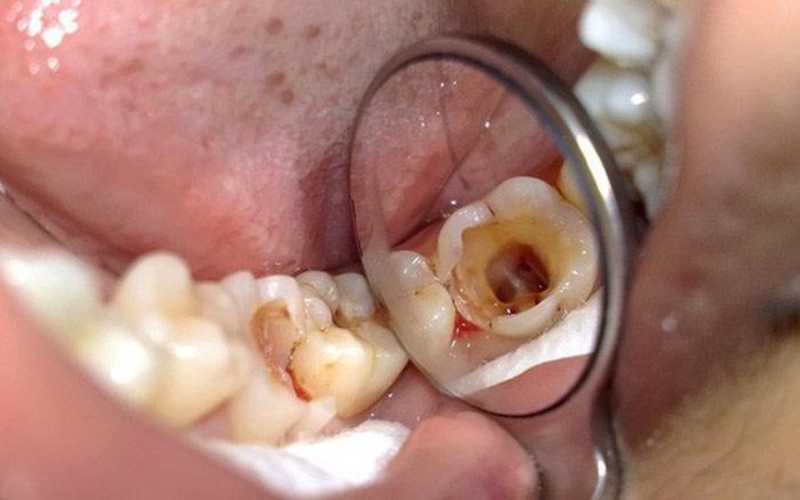

Sâu răng là bệnh lý răng miệng phổ biến nhất hiện nay, chúng được gây ra bởi vi khuẩn Streptococcus mutans. Loại vi khuẩn này lên men, tạo axit khiến men răng bị bào mòn, sau đó ăn sâu vào ngà răng trở thành sâu răng, ban đầu chỉ là những vết đen nhỏ, sau đó xuất hiện các lỗ với kích thước khác nhau trên bề mặt của răng.

Răng hay bị sâu nhất là răng hàm do vị trí của chúng nằm sâu bên trong rất khó vệ sinh. Sau khi ăn uống, các loại vi khuẩn có hại tấn công men răng làm cho răng hư hại theo thời gian. Nếu không có biện pháp chữa trị kịp thời, sâu răng sẽ lan rộng và ảnh hưởng tới các răng bên cạnh gây mất thẩm mỹ cũng như kéo theo các bệnh lý về răng miệng nghiêm trọng khác.